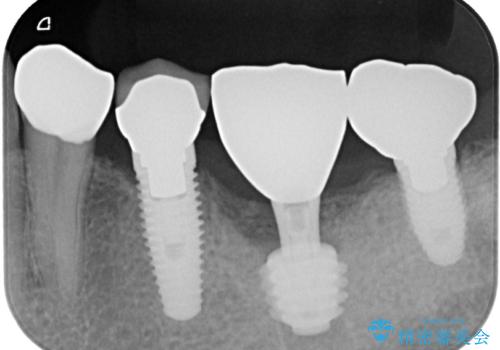

インプラント埋入時に植立具合の安定性を測定したところ、十分な数値が得られたため、速やかに仮歯を装着して咬合回復をさせることができました。

抜歯を含めた外科処置を1回に抑えることができ、あっという間に治療を終えることができました。